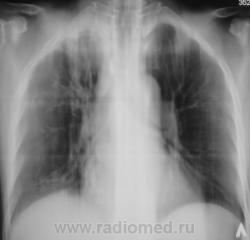

БОМЖ.

Еще контроль через 6 месяцев.